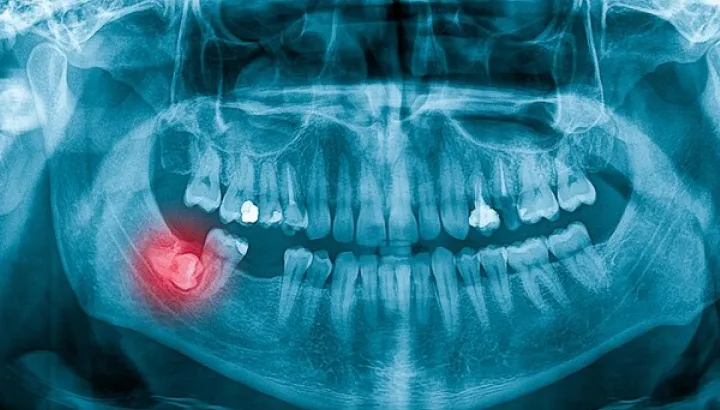

Comfort, safety, and precision are at the forefront of our wisdom tooth removal treatments. Whether a single or multiple extraction, our procedure is the most effective way to relieve pain, prevent infection, and protect surrounding teeth for long-term oral health.

Removing wisdom teeth at iCube Dental is a precise and technique-sensitive procedure that requires professional expertise and careful planning.

Each tooth is carefully extracted using advanced methods and laser-assisted technology, ensuring minimal discomfort and faster healing. This approach protects surrounding teeth and maintains proper jaw alignment, allowing you to eat, speak and smile comfortably. Wisdom tooth removal at iCube Dental not only relieves pain but also prevents infection, overcrowding, and potential oral complications—supporting long-term oral health and a confident smile.